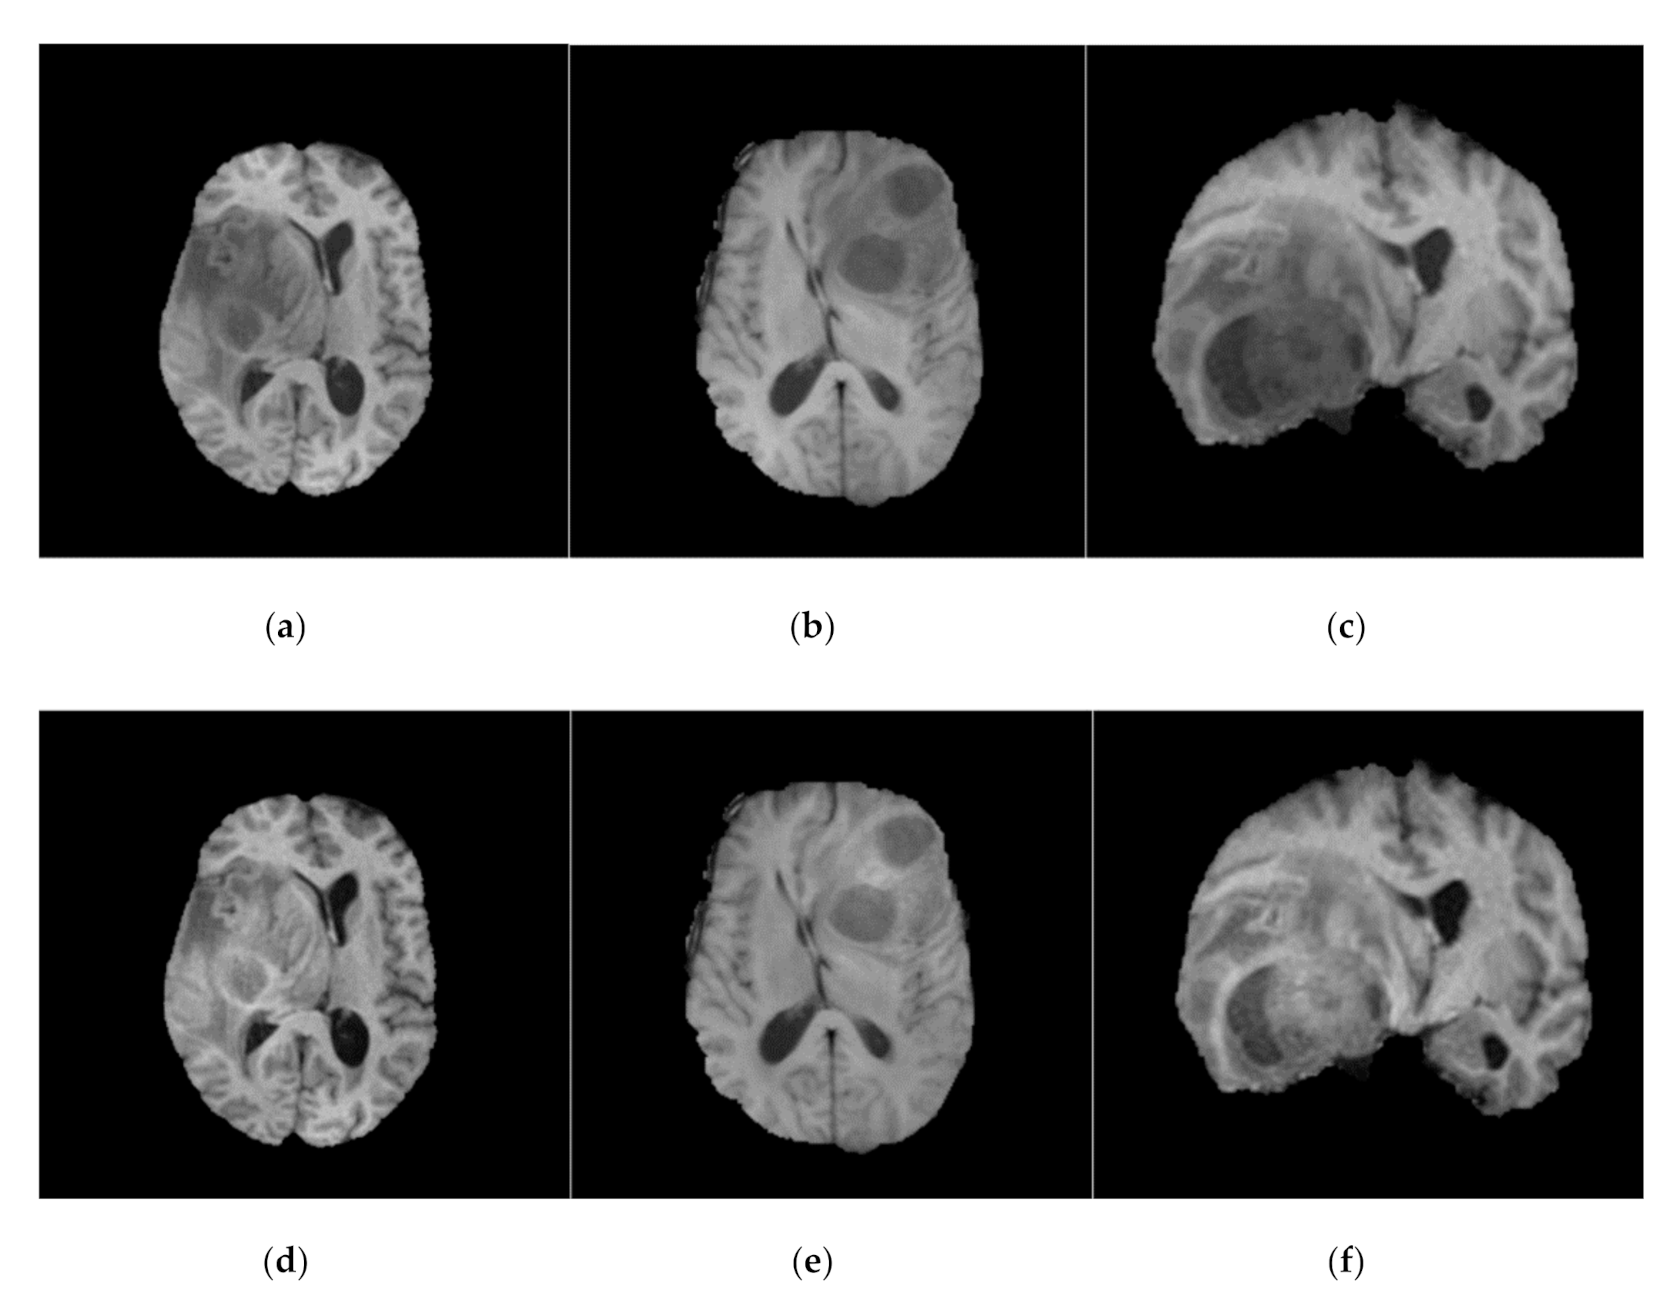

Similar to Kamnitsas et al. [13], N4ITK [7] was employed on BraTS-2013, BraTS-2015, and BraTS-2018 datasets as a pre-processing step. N4ITK [7] is also applied to this work to overcome the bias field distortion and variations in the magnetic field. Sample images from BraTS-2018 dataset before and after bias field correction are shown in Figure 1.

Figure 1.

Before (top row) and after (bottom row) bias field correction. Each MR image in the top row (a–c) has the corresponding bias field corrected MR image (d–f) in bottom row. All the images shown here are FLAIR (for fair comparison).